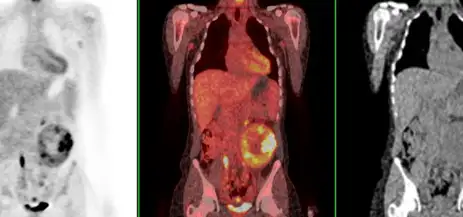

Image: The image on the left is a PET scan, the image on the right is a CT scan and the image in the middle is a PET fused with a CT.

One example of hybrid imaging is a PET scan. We use a radioactive glucose because it is very valuable in locating tumors. Almost all tumors use more of the sugar glucose than adjacent normal tissues. Pictures that show concentrations of radioactive glucose aid physicians in finding tumors. The location of tumors is even more accurately determined when CT images and nuclear medicine images are obtained at the same time.

The imaging study begins when the radioactive glucose (also called FDG) is injected into a vein. About one hour later, a precision nuclear medicine scanner called a PET scanner is used to make 3D pictures of the pattern of concentration of glucose in the body. As part of the same examination, a CT scan is performed with the patient in the exact same position in the scanner. The nuclear medicine and CT images can be then fused into a “hybrid” image, with the nuclear medicine images in color, overlaid on the CT images in black and white. In this way, the extremely sharp CT images are combined with the tumor-locating properties of the radioactive glucose, creating a particularly accurate method for locating tumor lesions called PET/CT.